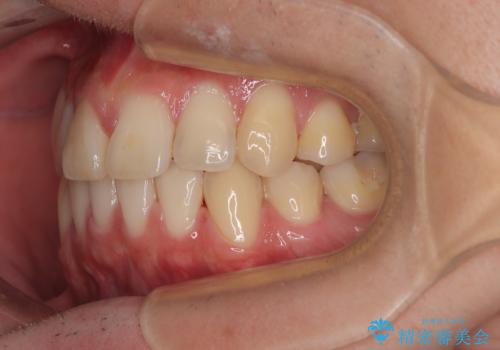

- 高校生の時に行った抜歯矯正の後戻りを気にして来院された患者様です。

インビザラインでの治療を希望されていて、デコボコの程度が中等度であり、安価なパッケージにて対応可能と判断されたため、インビザライン・モデレートを用いて矯正治療を行うこととしました。